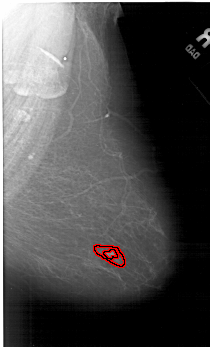

FILE: A_1255_1.RIGHT_MLO.OVERLAY

TOTAL_ABNORMALITIES 1

ABNORMALITY 1

LESION_TYPE MASS SHAPE IRREGULAR MARGINS ILL_DEFINED

ASSESSMENT 5

SUBTLETY 4

PATHOLOGY MALIGNANT

TOTAL_OUTLINES 2

BOUNDARY

CORE

FILE: A_1255_1.RIGHT_CC.OVERLAY